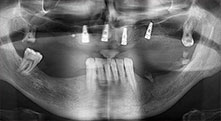

Piezomed B6

La cresta alveolare è stata incisa su entrambi i lati tramite piezochirurgia (strumento utilizzato: Piezomed B6). Gli impianti sono stati posizionati con la stessa procedura e l'osso peri-implantare è stato costruito con la tecnica GBR.

impianti

I quattro impianti sono fissati come programmato. I molari mascellari distali possono comunque essere utilizzati per fissare la protesi in linea introdotta un mese dopo l'impianto.